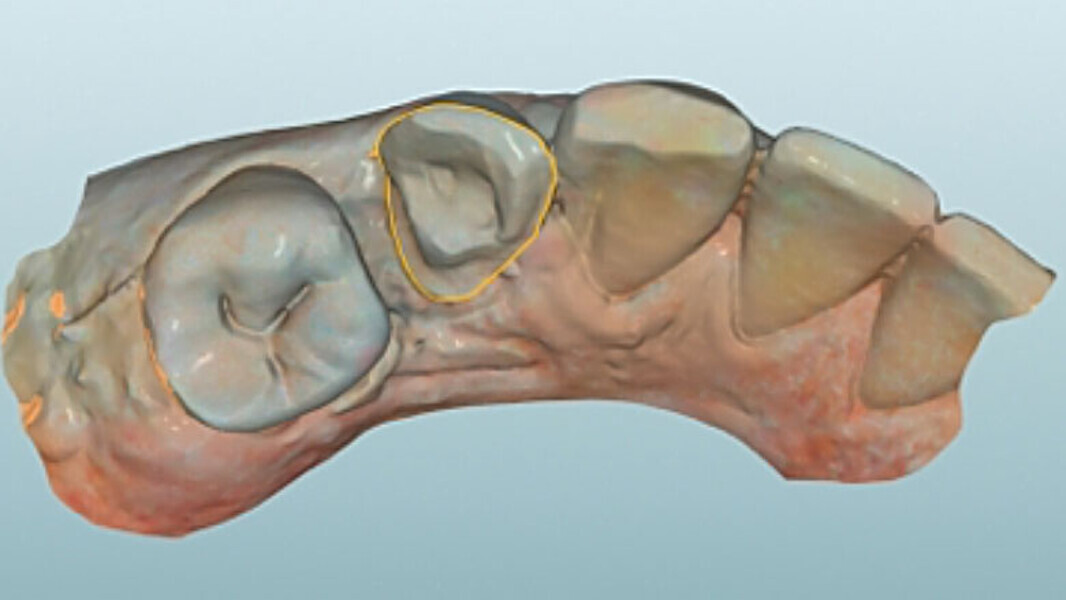

Fig. 5. Tras el escaneo intraoral se estableció el límite de la preparación.

Fig. 8. Vista oclusal de la endocorona virtual en el software CAD.